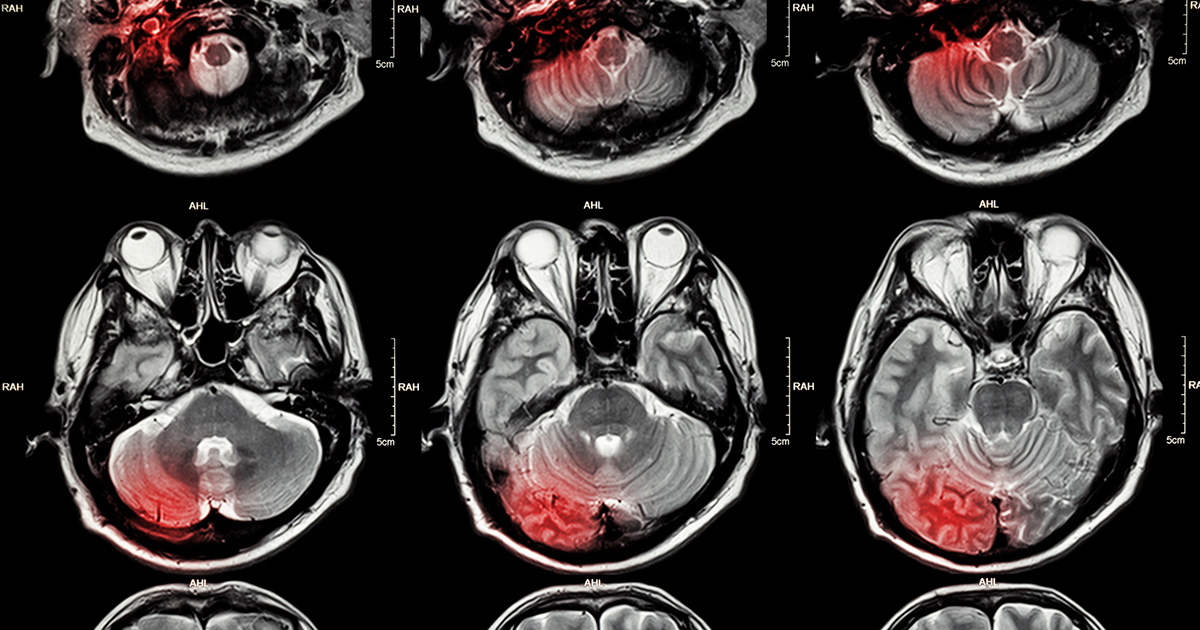

Causes Of Cerebral Edema

Cerebral edema, also known as swelling in the brain, is a life-threatening condition. When the brain swells, it can set off a chain of events, and the side effects are seen throughout the body. The stress of the injury can magnify the body's response or negate it entirely and make the issue harder to treat. Early management and treatment are crucial to improving the patient's prognosis. Learning more about the underlying conditions can help medical staff recognize the signs and symptoms sooner. Once those are treated, the edema should hopefully resolve, giving the patient a better chance at making a full recovery.